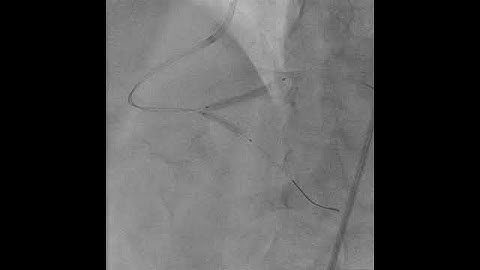

Complex PCI Case Study: Part 3 - Stent Deployment with Guide Support